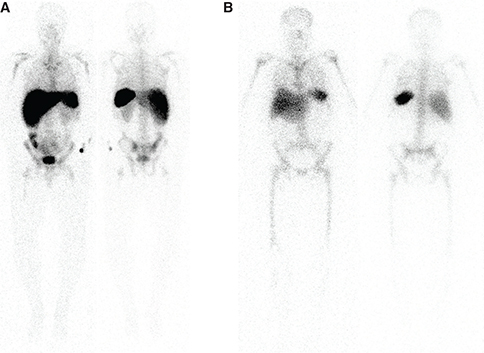

18F-FDG

Fig 3

Figure 3 Normal biodistribution of 18F-FDG, but with an enlarged spleen. Note the prominent brain activity, lower-level blood pool activity, more prominent liver activity and physiologic excretion along the urinary tract. Tonsillar, cardiac and bowel activity can be variable.